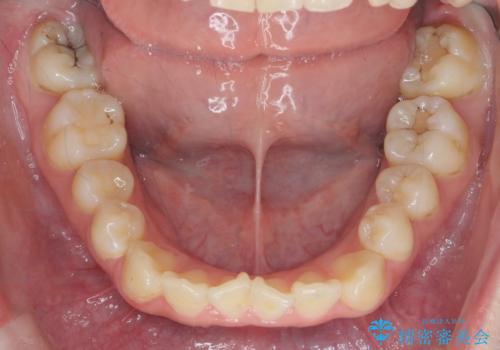

マウスピースで行う出っ歯の改善 後方移動

- 前歯の角度 奥歯の噛み合わせの改善をするために、矯正治療を希望され来院されました。

右側奥歯は上顎が相対的に前方に位置し(上顎前突)、そのため前歯の角度も突き出たようになり出っ歯のように見える状態でした。

マイクロインプラントを用いて、上顎奥歯を後方に移動させることで噛み合わせ・前歯の角度を改善していきます。